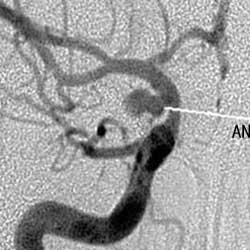

根據腹痛、消化道出血、黃疸及右上腹搏動性腫塊等特徵性表現,結合病史的分析,最後借選擇性肝總動脈造影或腹腔動脈造影確立診斷。

上消化道X線造影,可有胃幽門部或十二指腸被推壓和移位徵象。確立診斷必須依賴於選擇性腹腔動脈造影。腹部平片有時可見蛋殼樣動脈瘤壁鈣化影核素肝掃描可區分肝組織和動脈瘤體間的關係。